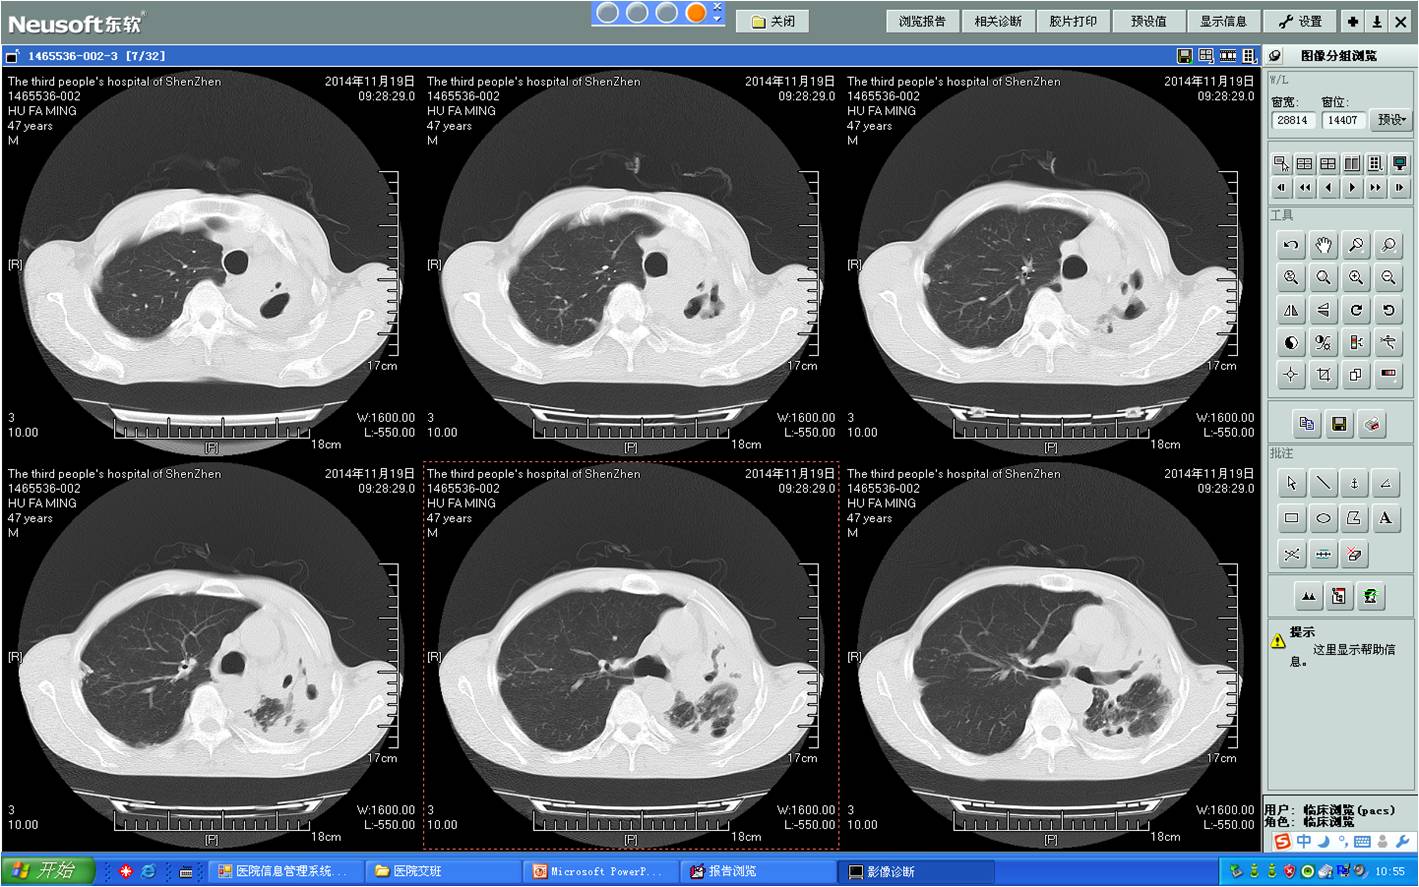

术前胸部CT

术前胸部CT